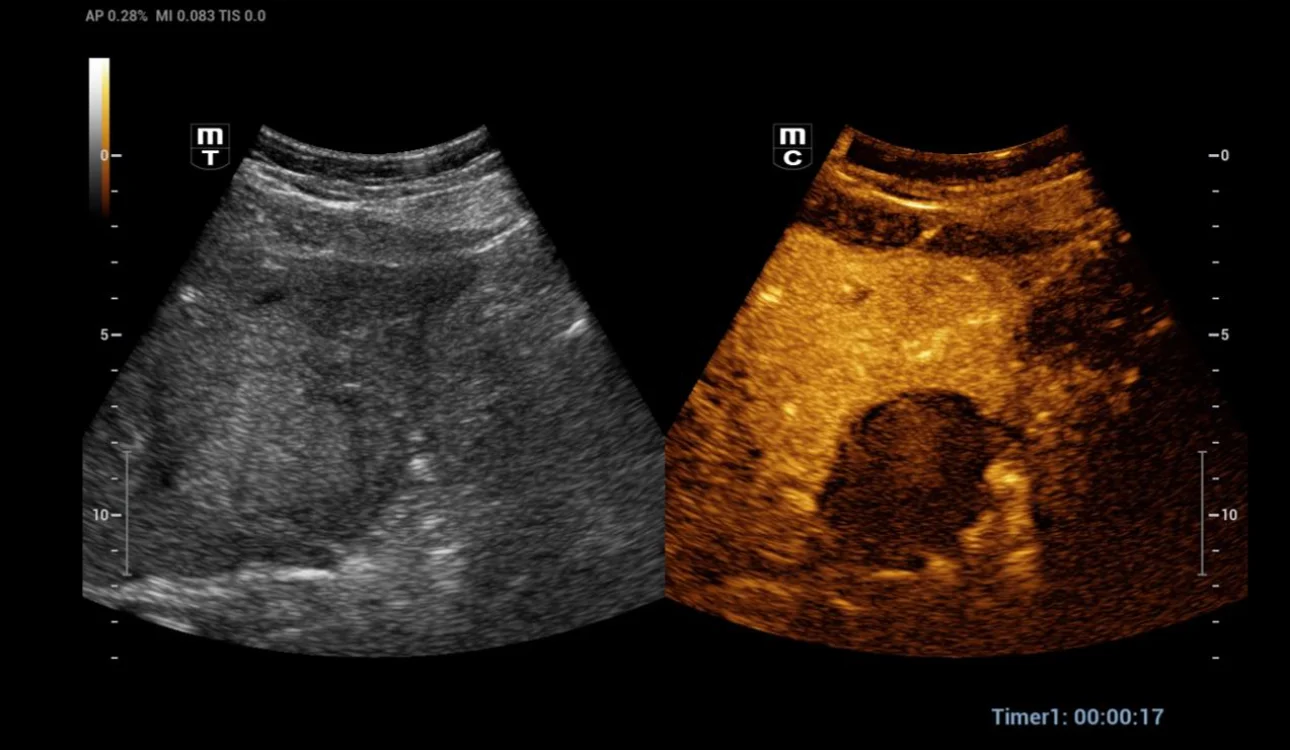

After a month, a CEUS exam was performed to assess the post-thermal ablation zone. The post-thermal ablation zone in the arterial phase after injection of 1.2 ml of Sonovue intravenously (Fig 2). A clear margin of necrosis developed from post-thermal ablation was visible. The necrotic region didn’t undergo contrast enhancement in any phase of the examination. In the portal phase (Fig 3-4), contrast washout was observed in the liver parenchyma adjacent to the ablation zone (arrows). Then a CT scan was performed to verify the case (Fig 5). A hepatic vein adjacent to the post-thermal ablation recurrence area was visible.

Fig. 2 The post-thermal ablation zone in the arterial phase (17th second). A clear margin of necrosis developed from post-thermal ablation was visible.